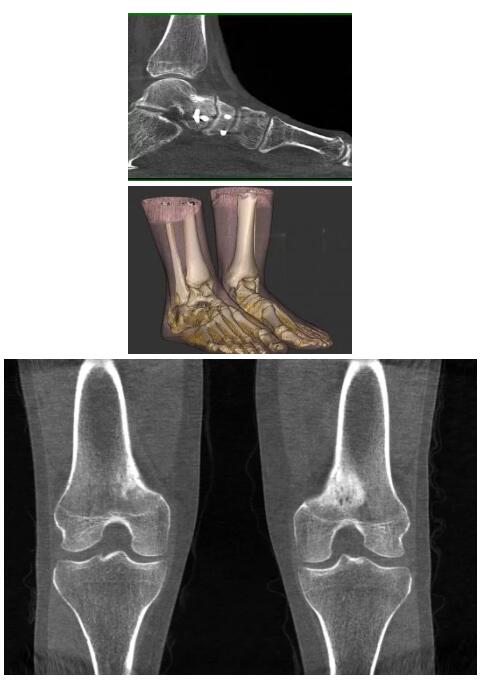

比如上面這款專用于足部和踝部掃查的CT成像系統(tǒng),患者在進(jìn)行CT掃查時(shí)只需要站在上面即可,雙腳站或者單腳站都可以,當(dāng)然,如果患者不是那么方便站著做完CT掃查,也可坐在上面。

這款CT掃查系統(tǒng)自帶屏蔽裝置,它的體積非常小,僅需要極小的空間即可,并不像常規(guī)CT那樣需要一間單獨(dú)的檢查室。此外,這種CT掃查的速度非常快,僅需30秒左右可以完成檢查,輻射劑量相對(duì)常規(guī)的CT要少許多,尤其適合醫(yī)院的骨科使用。

而患者站著做足部或者踝部做CT檢查還有個(gè)好處是,可以檢查患者在負(fù)重的情況下,骨關(guān)節(jié)的真實(shí)情況,而躺著做CT掃查時(shí)未必能看出來(lái)。負(fù)重CT掃查特別是對(duì)于受傷的運(yùn)動(dòng)員或者舞蹈員來(lái)說(shuō)意義更大,能夠更準(zhǔn)確地評(píng)估傷情,幫助他們盡早復(fù)原。

另外一款被稱為世界上最小的CT,它的重量?jī)H300磅,不僅能夠掃查足部,還可以檢查膝蓋和上肢等。

這款CT使用非常方便,通過(guò)上下移動(dòng)保持與患者的手臂或者雙腿齊平,掃描快速,僅需要30秒左右就可以完成掃查。

以上介紹的CT均來(lái)自國(guó)外同一家公司,這些CT均配置了可視化軟件,可以進(jìn)行切片、3D重建以及大型CT附帶的所有典型的操作功能。

以下是這些“特立獨(dú)行”的CT所拍出來(lái)的圖像: